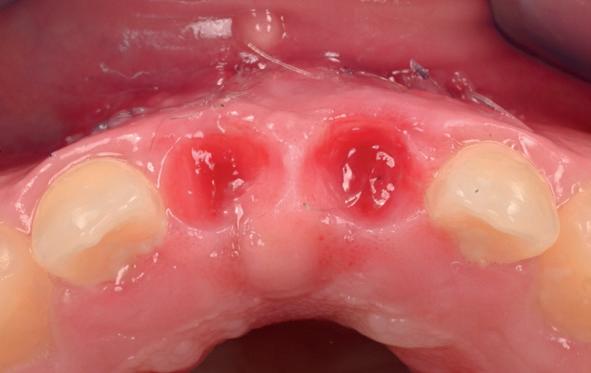

Vervaardigen essix retainer met dummies waarbij er een emergence profile van de 11 en 21 werd gevormd door eivormige dummies 4 mm in de gingiva te plaatsen

Na 4 weken intra-orale scan voor de etsbrug en kleurbepaling bij de technicus

16. Creëren van een duidelijke indeuking in de mucosa voor emergence profile